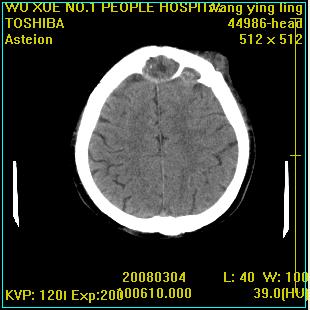

标题: CT12023:女,50岁,头部包块二月,伴轻微头痛,不伴发热。 [打印本页]

标题: CT12023:女,50岁,头部包块二月,伴轻微头痛,不伴发热。

这种病例还是比较多见,起源于颅骨板障,向颅内和颅外生长,考虑血管瘤或嗜酸性肉芽肿,要是有增强ct就好了。

多发溶骨性破坏,骨嗜酸性肉芽肿可能,转移瘤待排除,建议进一步检查。

破坏区边界较清楚,还是考虑良性病变---嗜酸性肉芽肿可能。

病灶呈溶骨性骨破坏,考虑嗜酸性肉芽肿可能转移瘤不除外建议追查病史并进一步检查